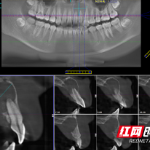

口腔科主任徐红为小茜做了详细的检查,发现这颗折断的前牙牙髓神经已经完全坏死,因为没有及时治疗,现在根尖区牙槽骨大面积被破坏,并且已经形成了囊肿,还波及到了相邻的牙齿。

牙外伤发生后如果不及时复查,可能发生牙髓慢性坏死,牙髓坏死后,细菌侵袭到根尖外部,感染范围逐渐扩大,继续发展会形成根尖囊肿、根尖肉芽肿等。如果不治疗的话,会进一步破坏吸收根尖周的骨头,甚至可能会累及邻牙,导致邻牙牙髓坏死,甚至松动、脱落。

听了徐红的解释,小茜的父母满是心疼与歉疚:“都怪我们没及时给孩子治疗呀!”徐红给小茜受伤的前牙进行了根管清理及囊液引流,控制牙齿炎症。由于根尖区破坏严重,后续将进一步进行根尖区的诱导治疗。